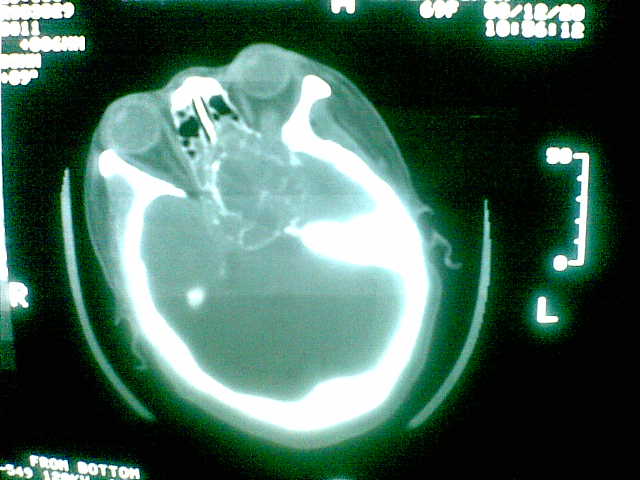

69岁 女 主因头痛就诊。大家看看起源于哪里啊

考虑脊索瘤(起源于蝶枕联合部)。